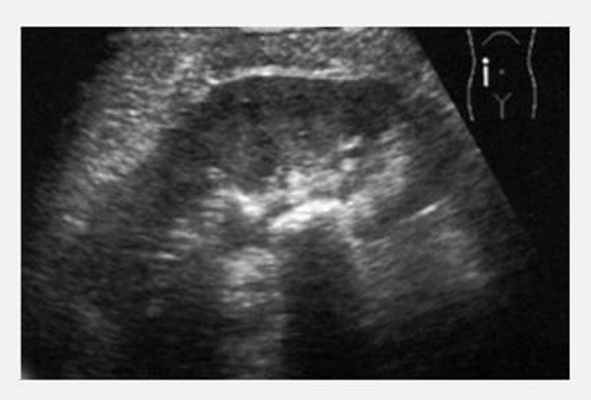

При УЗИ оценивается расположение почек, форма, контуры, размеры,

состояние чашечно-лоханочной системы, наличие дополнительных образований и

включений. В отличие от рентгеновского метода исследования УЗИ дает возможность

визуализации паренхимы почек, оценки ее структуры и выявлении в ней

морфологических изменений. Наиболее часто при проведении УЗИ почек и мочевого

пузыря выявляются аномалии развития, признаки воспалительных заболеваний (острого

и хронического пиелонефрита, гнойных поражений почек). При мочекаменной болезни

УЗИ почек высокоэффективна в выявлении конкрементов.

При УЗИ визуализируются камни любого химического состава, в то время для

рентгенологических методик камни, состоящие из мочевой кислоты, остаются невидимыми.

Также УЗИ информативно при определении уровня локализации конкремента,

уродинамических осложнениях мочекаменной болезни – обструкции, супрастенотическом

расширении мочевых путей.

При проведении УЗИ врач оценивает выраженность диффузных изменений

почечной паренхимы, выявляет кисты, доброкачественные и злокачественные опухоли. УЗИ информативна